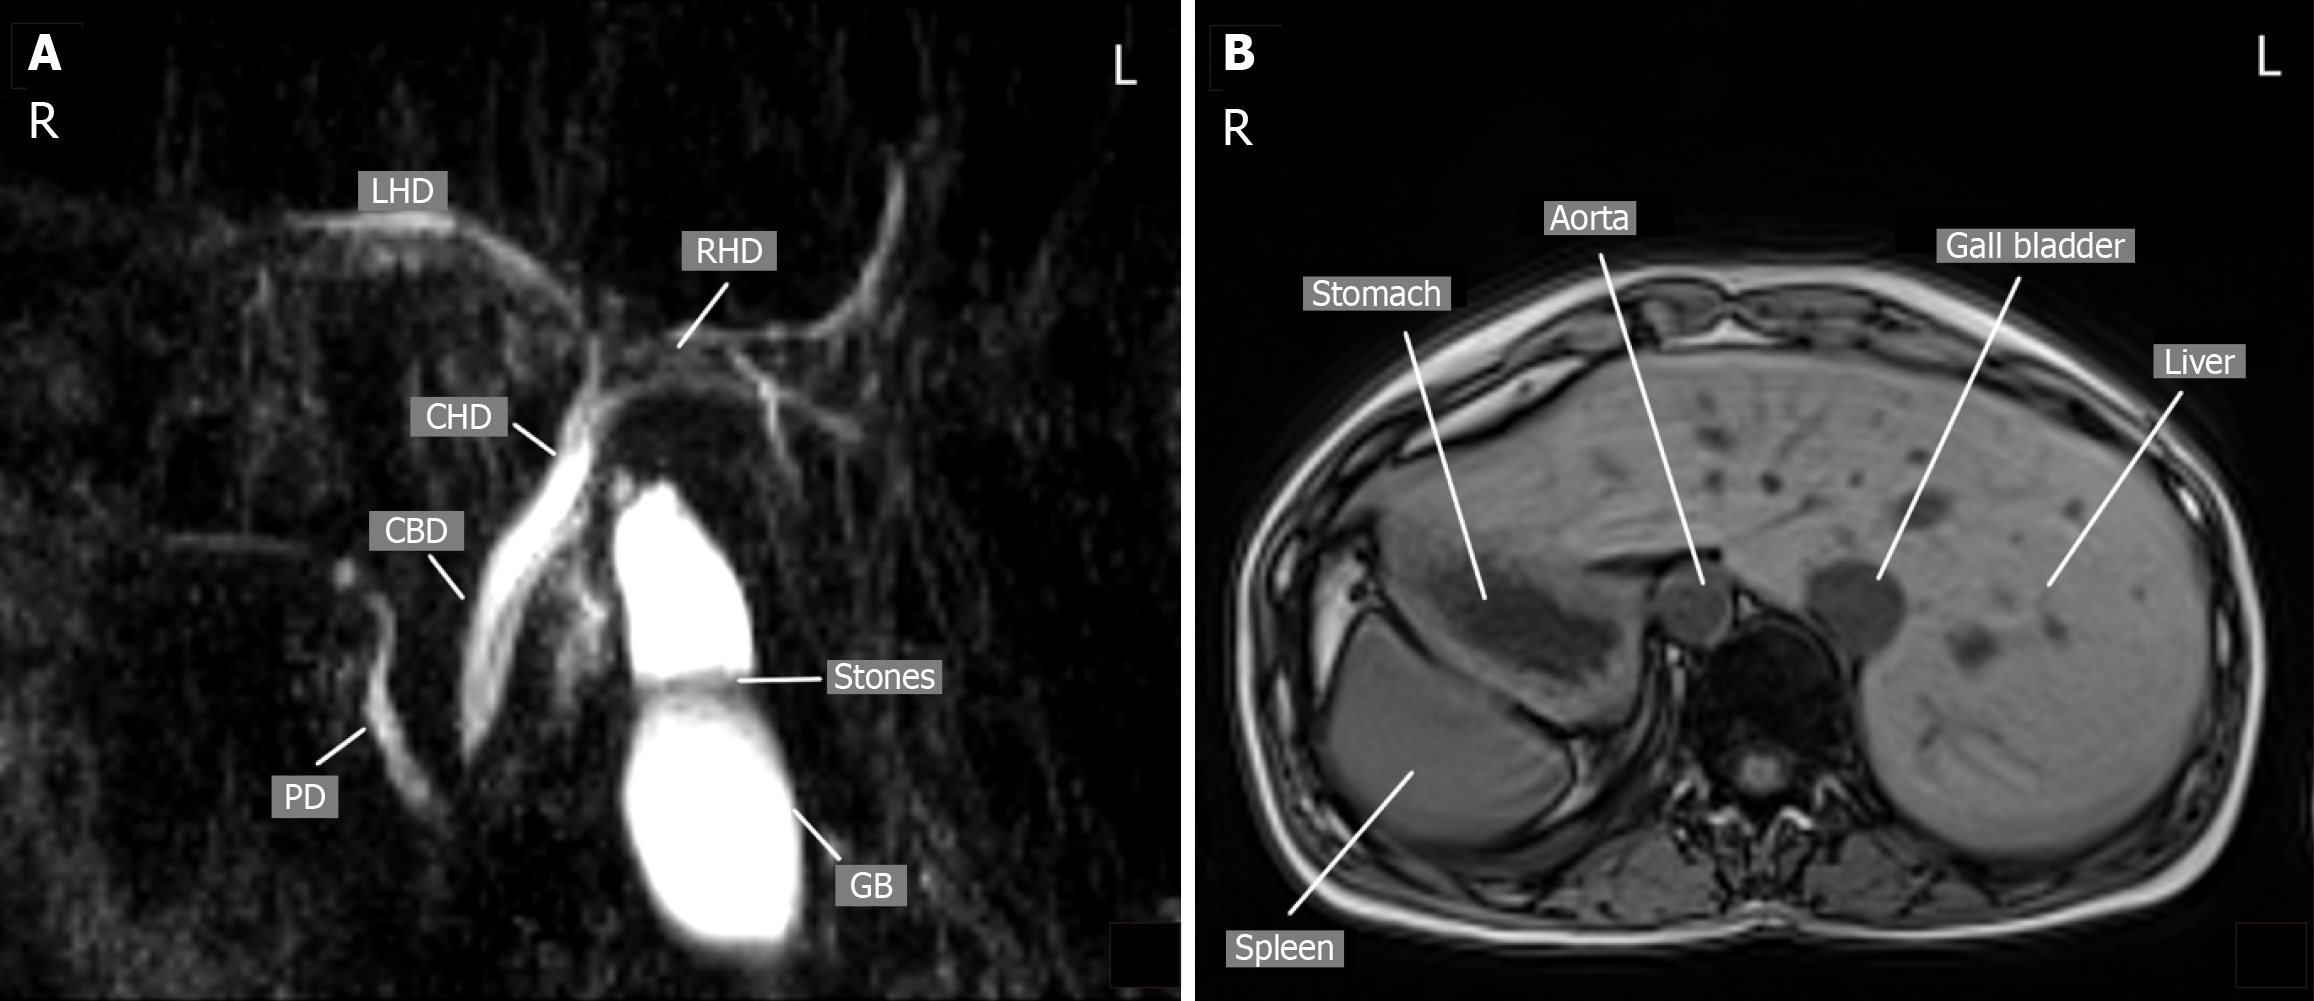

Case 2: Abdominal ultrasonography revealed gallstones and distal common bile duct calculi. Imaging confirmed SIT (Figure 3).

Symptomatic cholelithiasis in SIT (case 1) and cholelithiasis with choledocholithiasis in SIT (case 2) (Figure 4).